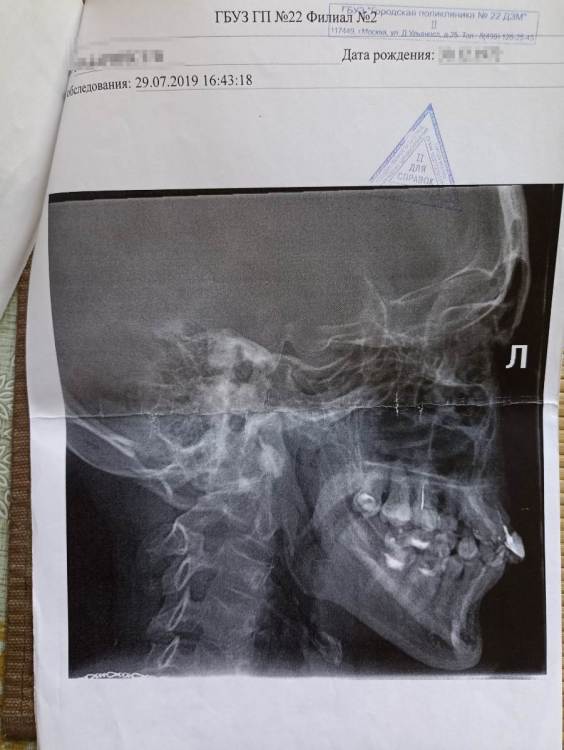

Moscowhelen Опубликовано 2 августа, 2022 Автор Поделиться Опубликовано 2 августа, 2022 Снимок челюсти сделан 2021. Ссылка на комментарий

Moscowhelen Опубликовано 2 августа, 2022 Автор Поделиться Опубликовано 2 августа, 2022 Возраст мой 49 лет. На данный момент удалены 1.5,2.4,3.7,4.6,4.7 зубы. Ссылка на комментарий